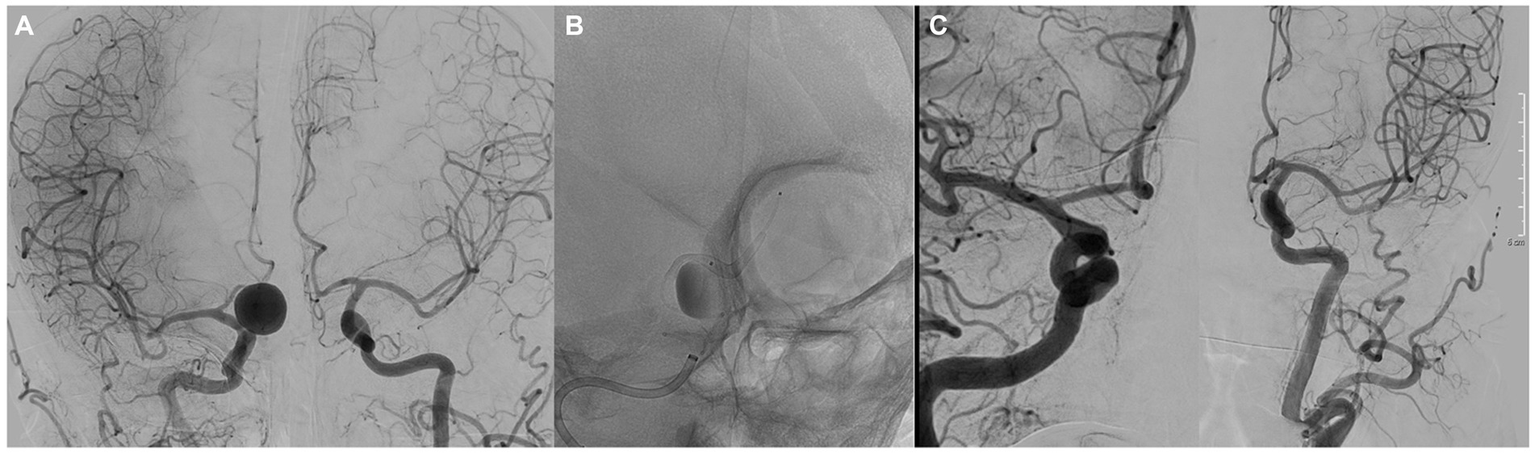

In the group with ruptured aneurysms, none of them suffered a re-rupture. Two patients presented with worsening of the mRs at 6 and 12 months, associated with the evolution of the disease. One patient presented with Fisher grade IV and World Federation of Neurological Surgeons (WFNS) grade V subarachnoid hemorrhage (SAH) secondary to dissection of the posterior inferior cerebellar artery. Treatment was performed on the same day as the SAH, an external ventricular drain placement and subsequent implantation of two 2.25 × 15 SVB devices. In the deferred angiographic controls performed, both devices remained patent, and complete occlusion was observed (OKM D) at 3 months, which was maintained over time. Final MRs score at 12 months follow-up was 1 point (Figure 3).

Figure 3

(A) Lateral angiography showing a dissecting aneurysm of the PICA. (B) Image showing the implantation of two 3.5 × 25 mm SVBs. (C) Angiographic control at 12 months showed complete occlusion of the aneurysm.

The angiographic follow-up was performed with brain magnetic resonance imaging at 3 and 6 months (MRA/Contrast enhanced MRA), and digital subtraction angiography at 12 months. Angiographic follow-up data were available for 50 patients, harboring a total of 50 aneurysms. In early angiographic follow-up (at 3 months),16/50 (32%) aneurysms showed complete occlusion (OKM D), and 12/50 (24%) showed near-complete aneurysm occlusion (OKM C). At 6 months, 23/50 (46.9%) (OKM D) and 17/50 (OKM C) aneurysms showed complete occlusion and near-complete aneurysm occlusion, respectively. At the 12 months follow-up, 33/50 (66%) and 14/50 (28%) aneurysms showed complete occlusion (OKM D) and near-complete aneurysm occlusion (OKM C), respectively (Figure 4). In summary, adequate aneurysmal occlusion was observed in 94% of all aneurysms after 12 months, and only 2% of the treated aneurysms remained morphologically unaltered without an apparent change in perfusion (OKM A).

Figure 4

(A) Anteroposterior angiography showing a saccular aneurysm of the right A1 artery. (B) Image showing the implantation of a 3.5 × 25 mm SVB. (C) Angiographic control at 12 months showed complete occlusion of the aneurysm.